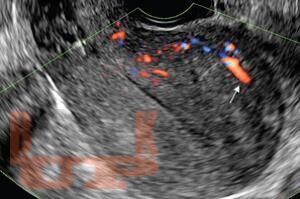

В учебном пособии на современном уровне освещены вопросы диагностики эндометриоза различной локализации. Предназначено для врачей акушеров-гинекологов с целью формирования научно-обоснованного подхода в диагностике эндометриоза и его локализаций с целью обнаружения заболевания на ранних стадиях и сохранения репродуктивного здоровья женщины.